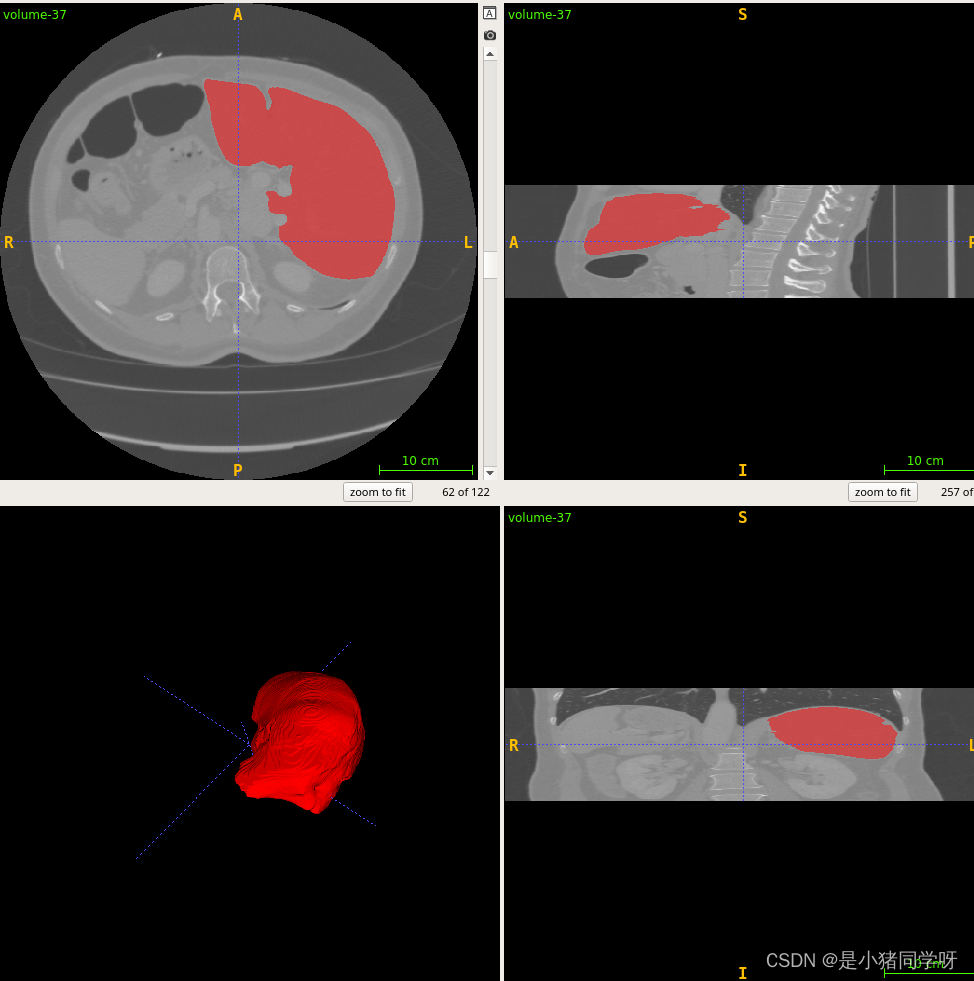

经过测试,肝脏和肝脏肿瘤分割系统的各项功能都能够正常工作,满足用户需求。在白盒测试方面,覆盖了网络结构、特征提取、特征映射、损失函数等方面,没有发现明显的问题。在黑盒测试方面,采用了等价类划分、边界值分析、因果图和错误推测等方法,测试结果表明系统的各项指标均符合要求,没有发现明显的问题。

本次测试结果表明,肝脏和肝脏肿瘤分割系统的各项功能都能够正常工作,满足用户需求。在白盒测试和黑盒测试方面,测试覆盖了网络结构、特征提取、特征映射、损失函数、上传CT影像、查看分割结果、后处理、性能评估、恢复测试、安全测试、强度测试和性能测试等方面,测试结果表明系统的各项指标均符合要求,没有发现明显的问题。